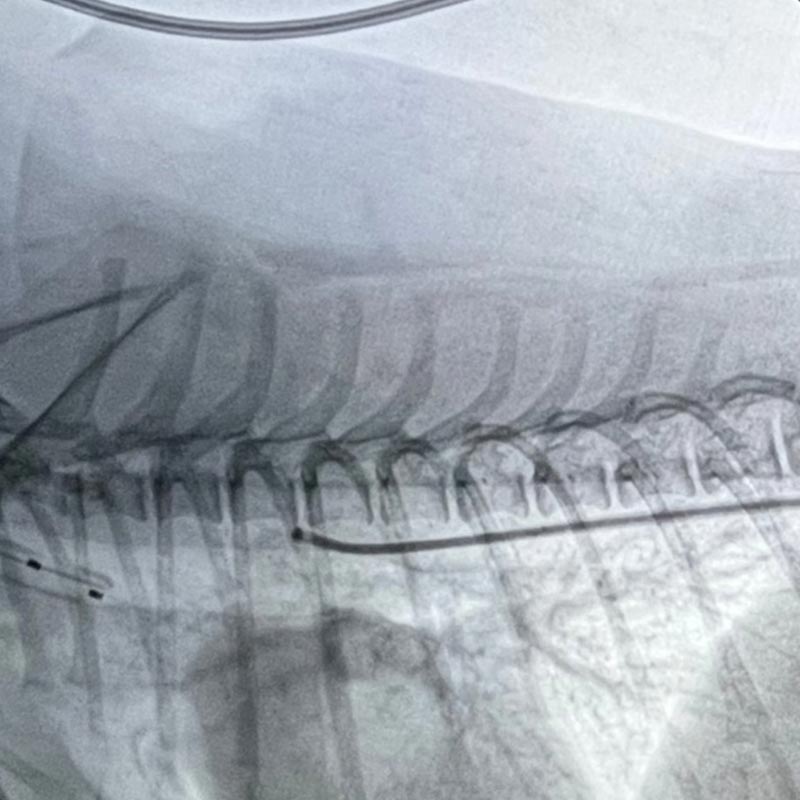

요도폐색 (Urethral Obstruction)

스텐트 삽입술 (요로 개방 유지)

• 인터벤션방식으로 조직 손상이 거의 없음

• 빠른 요로 흐름 회복으로 통증·신장 손상 감소

• 기존 수술 방법에 비해 재발·협착률 감소 효과 기대